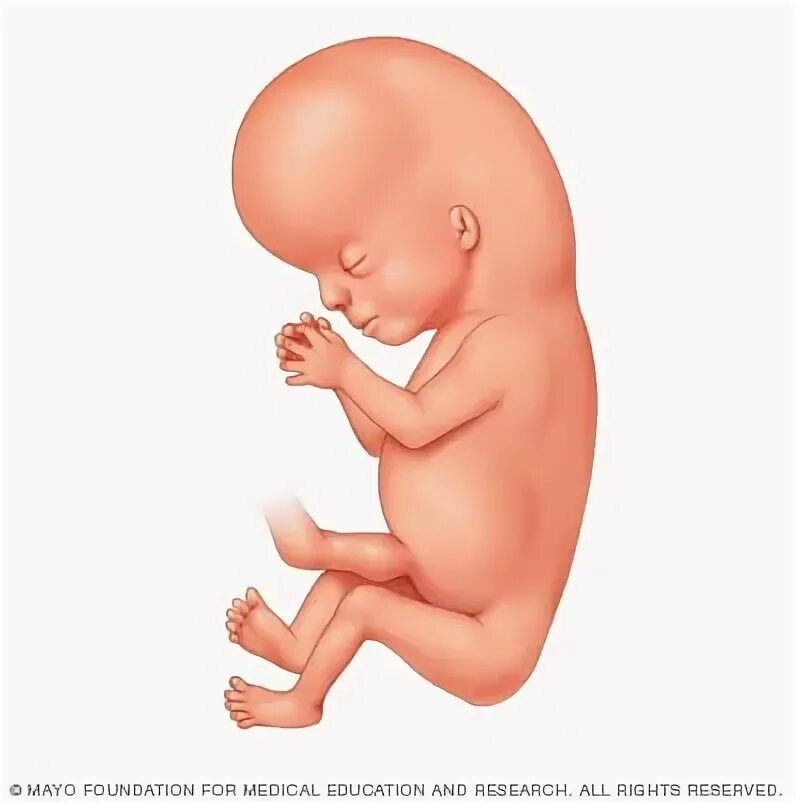

10 week old